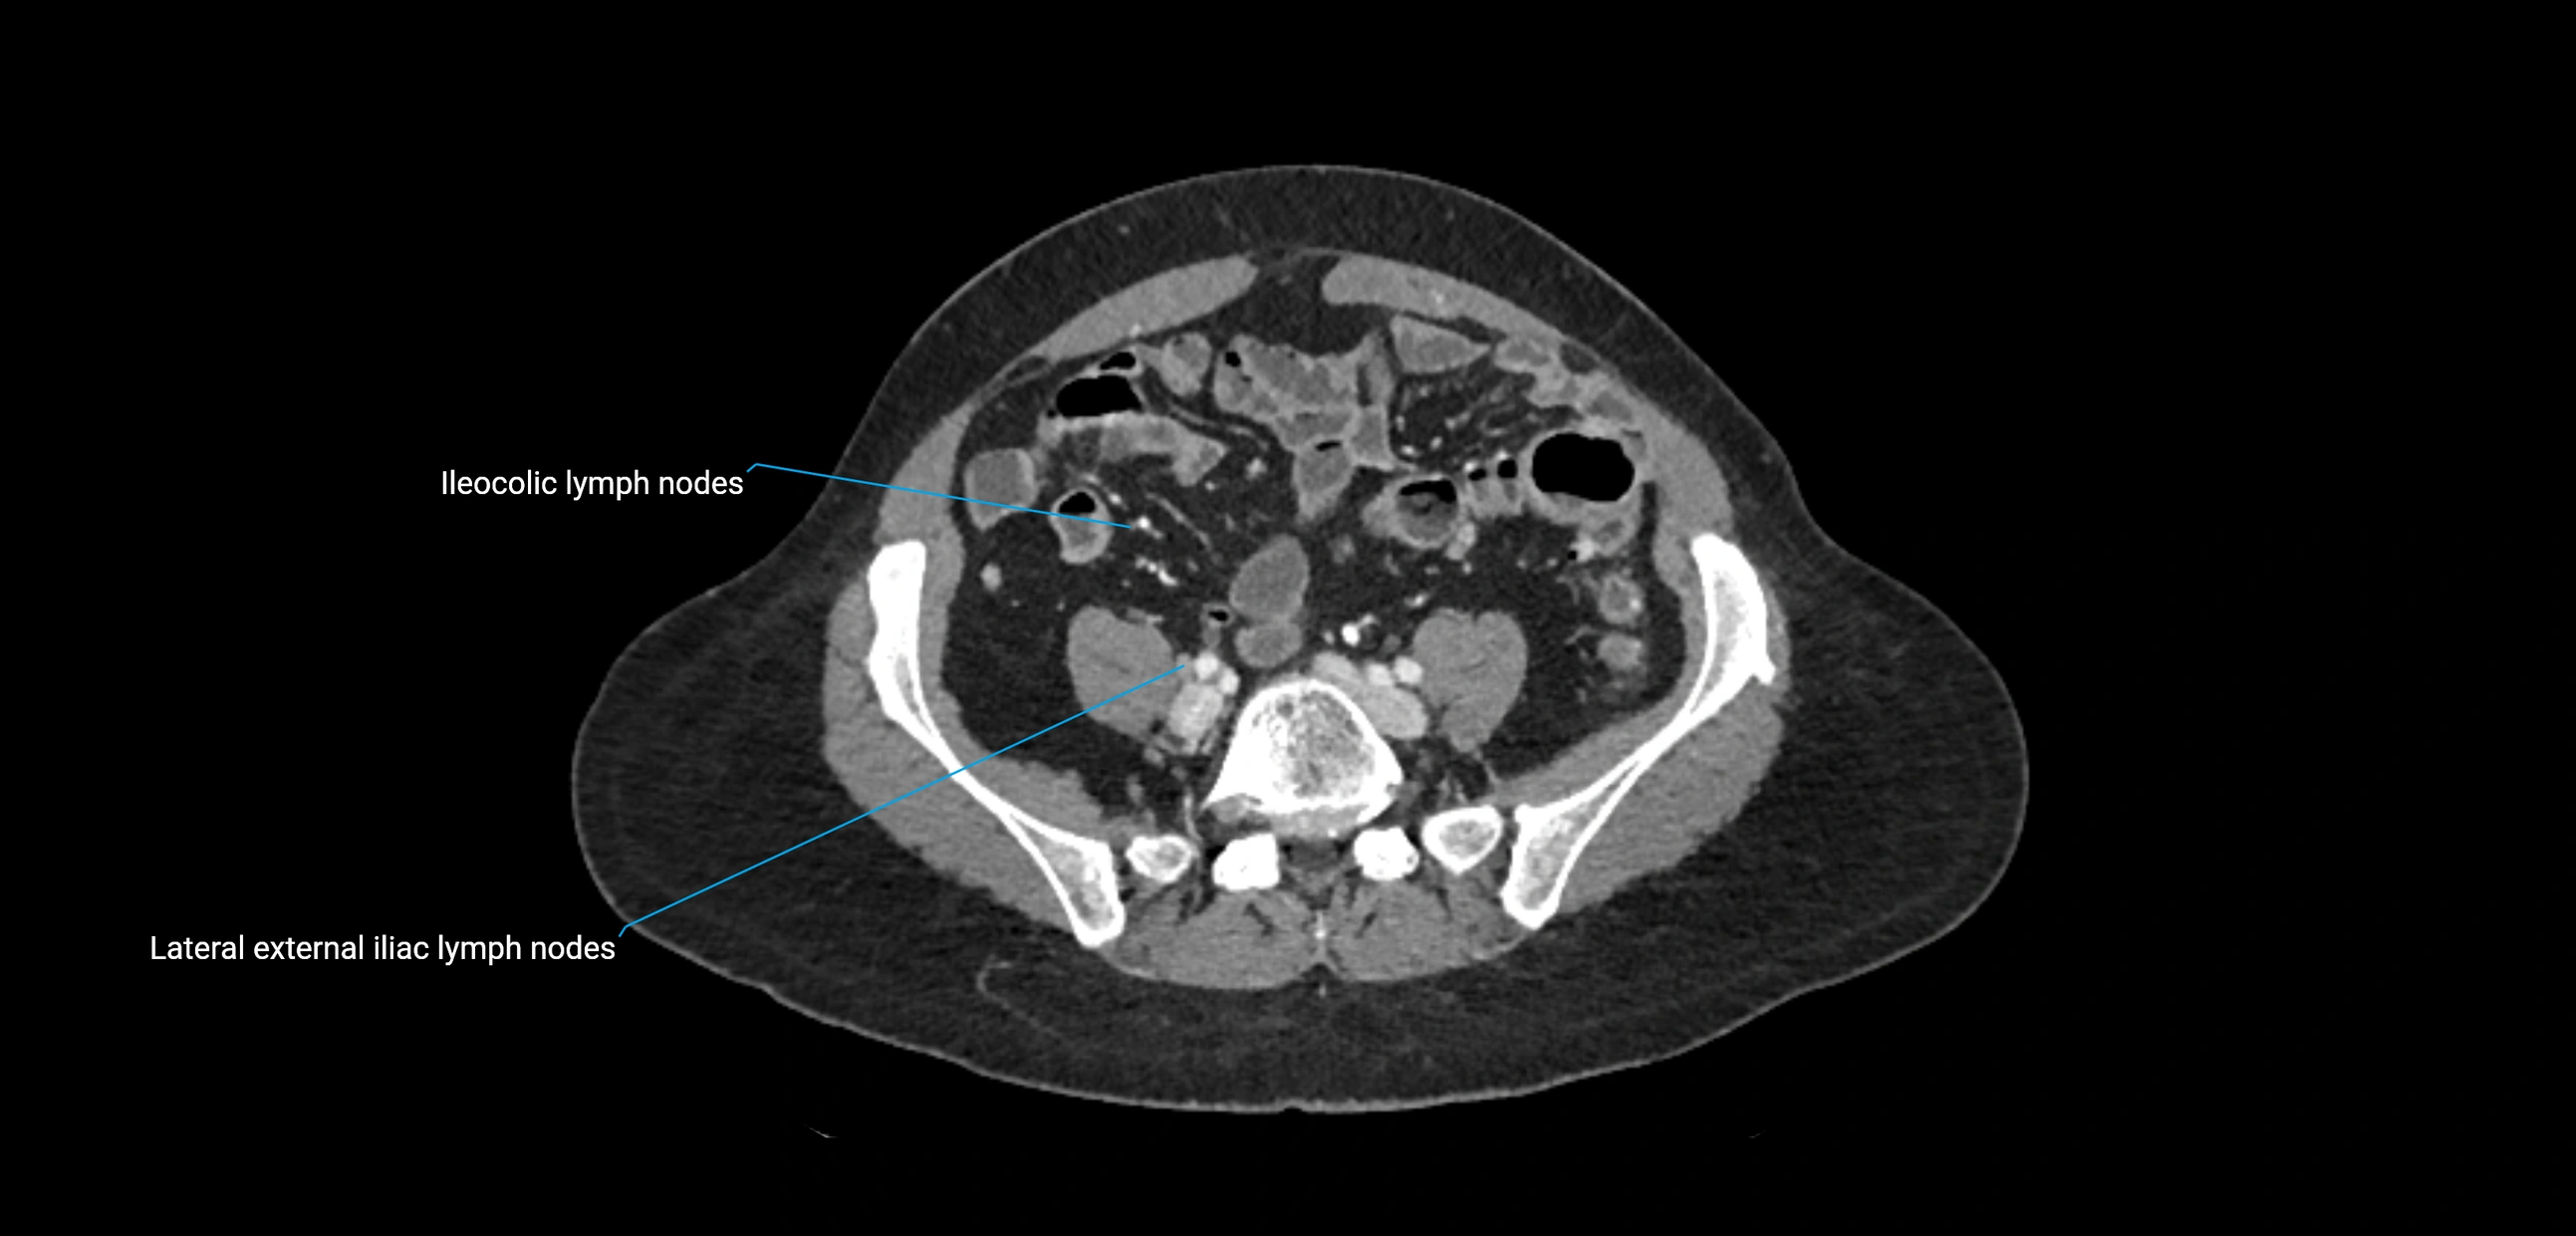

CT Appearance

CT Pre-Contrast:

• Nodes appear as soft-tissue density nodules adjacent to the aorta and IVC

• Calcification may be seen in chronic infections (e.g., tuberculosis)

CT Post-Contrast:

• Normal nodes enhance homogeneously

• Malignant nodes may show heterogeneous enhancement, central necrosis, or conglomerate formation

• Size >1 cm short axis is suspicious, though morphology and distribution are equally important

CT Venography (CTV):

• Demonstrates nodal encasement or compression of adjacent vessels (aorta, IVC, renal veins)

• Useful in staging testicular and ovarian malignancies

• Provides 3D reconstructions for retroperitoneal lymph node dissection planning

CT image

image